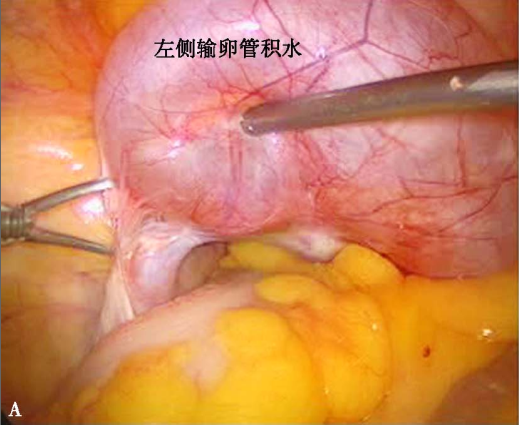

输卵管积水和输卵管卵巢囊肿

A左侧附件周围大量膜性粘连,左输卵管伞端闭锁,浆液性渗出物聚集形成输卵管积水;B左输卵管伞端闭锁、浆液性渗出物聚集,并与卵巢粘连、包裹形成输卵管卵巢囊肿